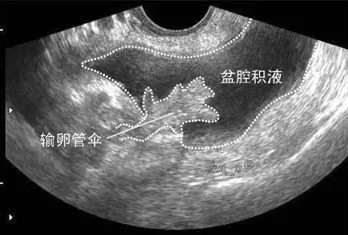

盆腔積液大多是盆腔存在炎性滲出物,常表現(xiàn)為小腹下墜、脹痛,腰酸腰痛、月經紊亂、不孕等,那具體盆腔積液是怎么引起的呢?盆腔積液是怎么回事?盆腔積液的危害有哪些?盆腔積液的產生主要可分為生理性因素和病理性因素兩種。

生理性盆腔積液是指正常的盆腔積液,不需要治療。人體的盆腔、腹腔并不是干巴巴的一塊「土地」,腹膜、大網膜、腸管等都會分泌一些液體,這些液體通常起到潤滑和保護盆腹腔器官和組織的作用。盆腔積液可通過 B 超檢查觀察到,如果積液的深度小于 3 cm,沒有其他不舒服的癥狀,通常是不需要處理的。

不孕是盆腔積液最常見的癥狀。如果盆腔炎導致輸卵管堵塞,就會出現(xiàn)不孕。